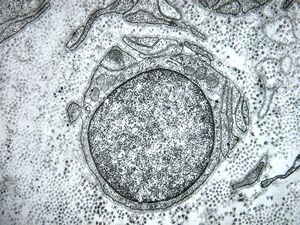

F,12y. | hypertrophic (onion bulb) neuropathy - n.suralis